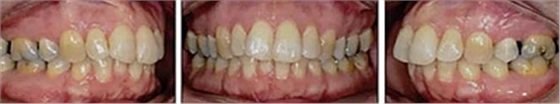

患者曾行正畸治療,現(xiàn)覺(jué)笑容不美觀前來(lái)就診?;颊哒嬗^及側(cè)貌示下頜發(fā)育不足,偏高角,唇閉合不全。上下頜中線(xiàn)齊。覆合、覆蓋4毫米。磨牙關(guān)系及尖牙關(guān)系II類(lèi)。上頜擁擠度4mm,下頜擁擠度6mm。4顆第一前磨牙在第一次正畸治療時(shí)已拔除。上下牙弓呈尖圓型,牙弓狹窄。

患者側(cè)貌改善,下唇唇肌緊張消失,上下唇可自然閉合。磨牙及尖牙關(guān)系糾正至I類(lèi),覆合覆蓋正常。上下頜弓型糾正至卵圓形,牙弓寬度增加。頭影測(cè)量分析示SNA角81.8°,ANB角3°。頭影測(cè)量重疊圖示下頜骨向后旋轉(zhuǎn),垂直面高度略有增加。